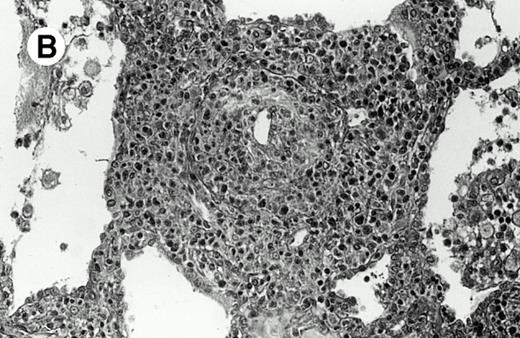

Three cases (cases no. 1 to 3) were located in the nasal cavity. The neoplastic infiltrate consisted of medium and/or large pleomorphic lymphoid cells (Fig 1)intermingled with variable numbers of small lymphoid cells, plasma cells, eosinophils, and histiocytes. Features of angiocentrism and angioinvasion, epitheliotropism, and areas of necrosis were observed in all three cases. Patient no. 4 presented with disease restricted to the lung and an open-lung biopsy was available. The neoplastic infiltrate was composed of large atypical lymphoid cells and was predominantly interstitial without extensive destruction of the normal architecture. Features of angiocentrism, angioinvasion, and epitheliotropism were present (Fig 2A and B). Case no. 5 involved the larynx, extending to the piriform sinus, the ventricle, and the arytenoid. One month later, the lymphoma disseminated to the subcutaneous tissue in the spinal region and biopsy specimens from both sites were available. The neoplastic cells were medium and large, with abundant clear cytoplasm and slightly irregular nuclei with dense chromatin. Epitheliotropism was present in the larynx mucosa. Small foci of necrosis and angiocentrism were seen without angioinvasion. Three patients presented with cutaneous disease. Cases no. 6 and 7 were comparable, as both histories started with necrotic subcutaneous nodules of the thigh, which on histologic analysis were characteristic of cytophagic histiocytic panniculitis without evidence of lymphoma (Fig 3A). Second excisional biopsies of cutaneous nodules obtained 7 and 5 months later, respectively, showed characteristic features of lymphoma in both cases (Fig 3B). However, in case no. 6, skin biopsy specimens showed an epidermotropic PML lymphoma extending to the dermis and the subcutaneous tissue, whereas in case no. 7, the neoplastic infiltrate consisted of a PSC confined to the subcutaneous tissue, admixed with benign histiocytes that showed phagocytosis. Patient no. 8 presented with recurrent skin lesions with spontaneous remission over a period of 10 years. The initial skin biopsies demonstrated an intense epidermotropic neoplastic infiltrate that extended to the superficial and deep dermis composed of atypical PML cells. All cutaneous cases displayed features of angiocentrism, but angioinvasion was observed only in case no. 6 and foci of necrosis in cases no. 6 and 8.

Pulmonary pleomorphic large-cell γδ T-cell lymphoma (case no. 4). (A) Atypical lymphoid cells involve the bronchiolar wall and epithelium; (B) features of angioinvasion; note the preservation of alveolar structures (lung biopsy specimen with hematoxylin-eosin stain); (C) neoplastic cells strongly express TCR γδ. (Immunohistochemical staining on frozen sections with anti-δTCR1 antibody, APAAP technique.)